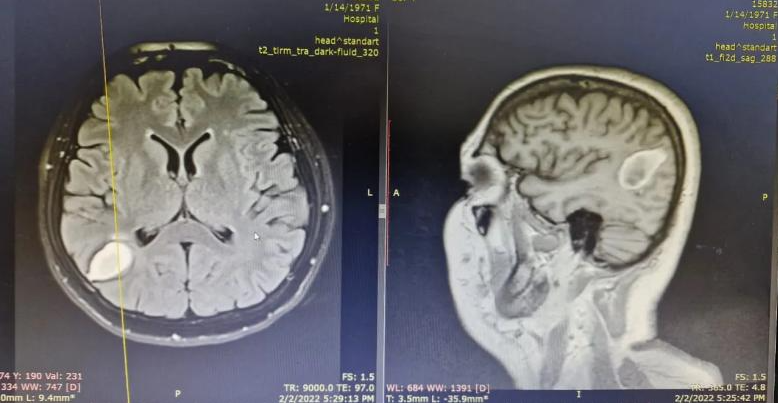

Վրացի բժիշկները կնոջ գլխուղեղում կենդшնի ճիճու են հայտնшբերել (Լուսանկար)

Երեք տարի արտերկրում մեր քաղաքացու մոտ ախտորոշվել է գլխեղի չորրորդ փուլի որոշումը, նրան առաջարկել են սպանել։ Կինը որոշել է վերադառնալ հայրենիք, հաղորդում է Euromedia24.com -ը որտեղ վրացի բժիշկները, հետազոտելով վիրահատելով հիվանդին և փոխարենը հայտնաբերել են 15 սանտիմետրանոց երիզորդ, շարժվում է ուղեղում.

Վիրահատությունը տեղի է ունեցել մի քանի օր առաջ և հիվանդին այժմ բավարար է, բժիշկները վիճակ են, որ նա գտնվում է նյարդաբանների և մակաբուծաբանների հսկողության տակ։